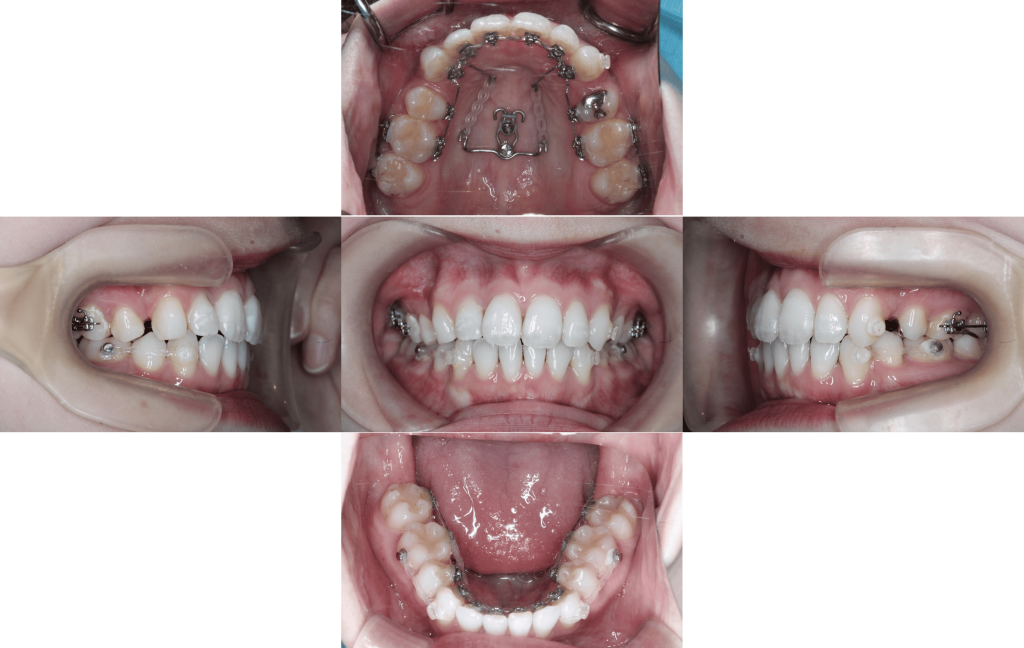

装置装着